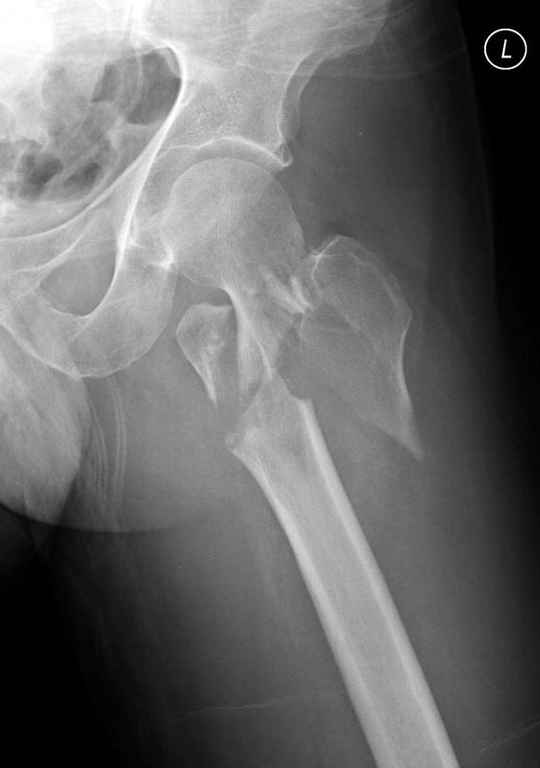

Предугадать распространение линий перелома при чрезвертельных и оскольчатых переломах трудно, поэтому для принятия правильного решения рекомендуется Компьютерно Томографические исследование.

При отсутствии КТ, снимок на вытяжении поможет увидеть общую картину расположения отломков, особенно потенциальные места введения импланта. Риск раскола в этом случае огромный, поэтому больной должен быть дообследован.

Здесь пара похожих случаев.